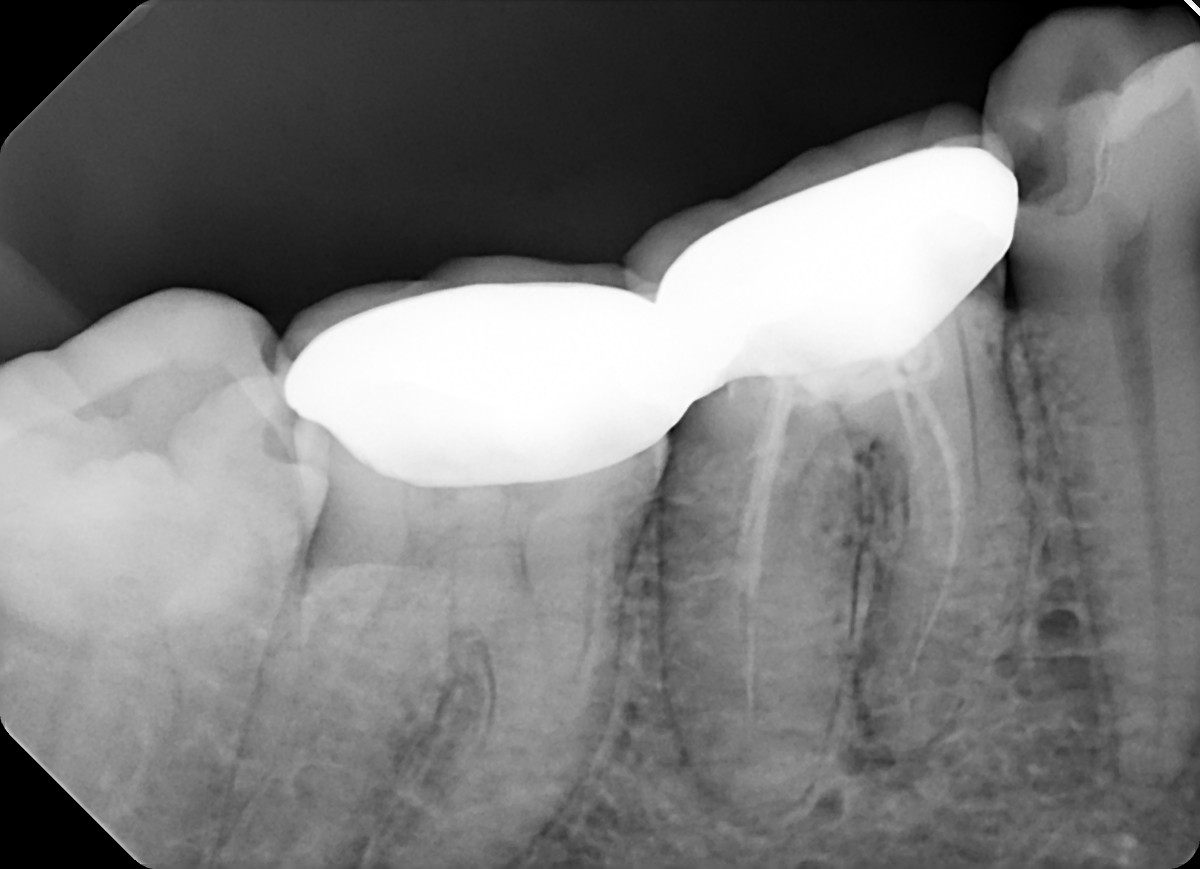

2. What option can be selected for the X ray bellow?